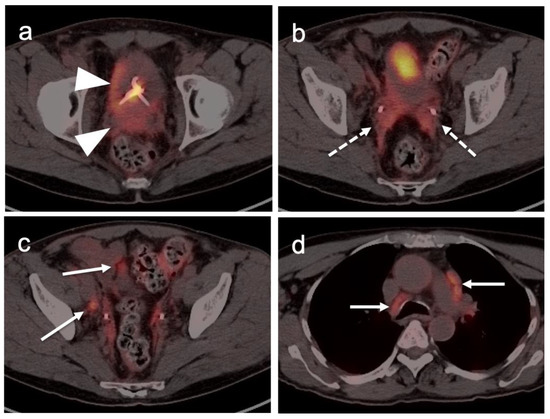

2.4. Cervical Cancer